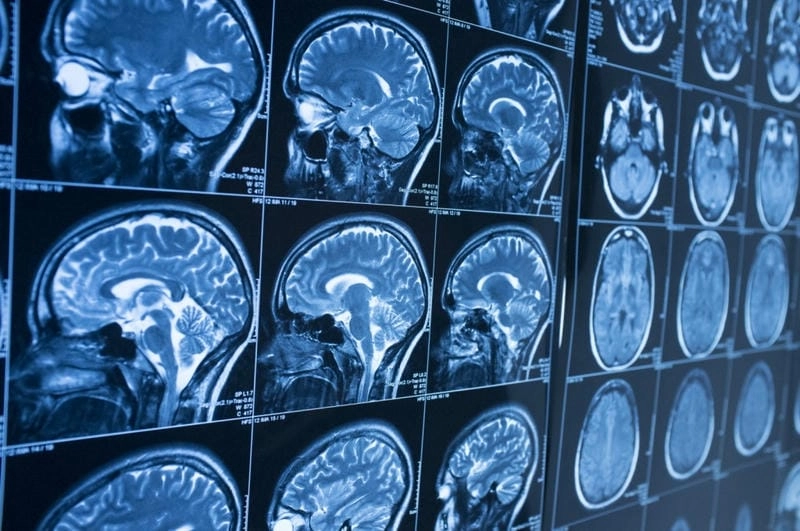

Hình ảnh bệnh Alzheimer giúp nhận biết sự thay đổi não bộ và biểu hiện lâm sàng của bệnh. Việc quan sát hình ảnh minh họa giúp người nhà và bác sĩ đánh giá giai đoạn, hỗ trợ chẩn đoán sớm và lên kế hoạch điều trị hiệu quả.

Quy trình chẩn đoán bệnh alzheimer minh họa bằng hình thực tế